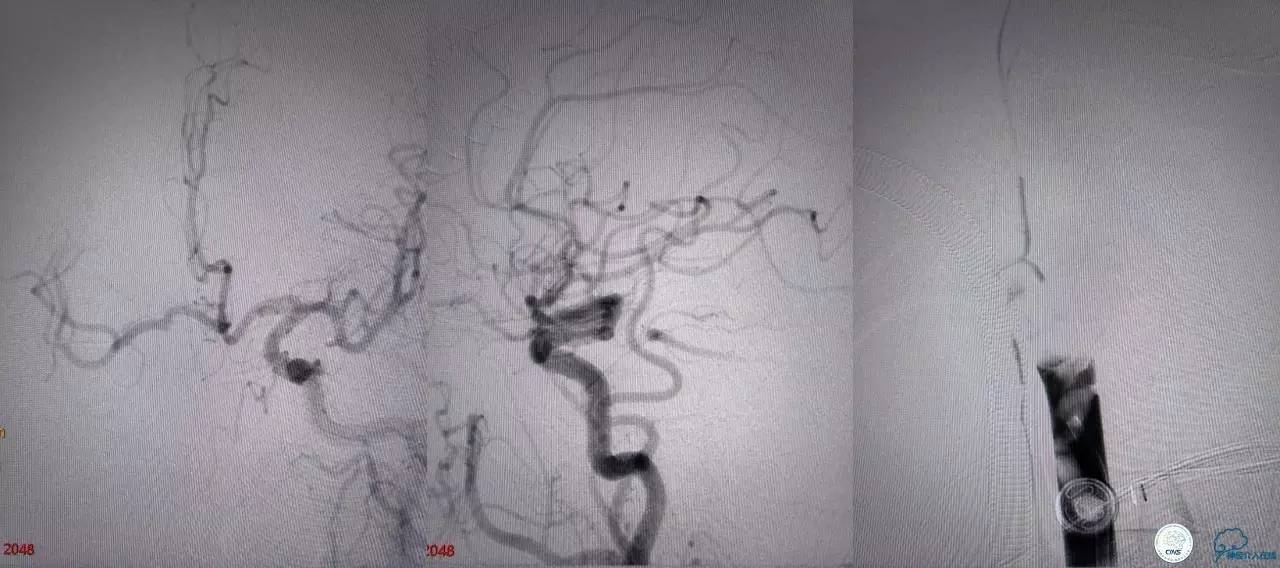

基底动脉顶端仍有大量血栓,双侧大脑后动脉未见显影,双侧小脑上动脉再通。再次取栓?还是动脉溶栓?

决定导管内给予替罗非班6ml,复查造影BA顶端仍闭塞,第二次取栓。

第二次取栓后可见基底动脉顶端仍有大量血栓,右侧大脑后动脉开通,但左侧大脑后未见显影且左侧小脑上动脉闭塞!

第三次取栓,支架放入左侧大脑后取栓。

第三次取栓后,左侧大脑后动脉开通,但是栓子再次栓塞右侧大脑后动脉,血栓在基地动脉顶端来回左右摆动,下一次,怎办?血栓负荷太多,能够使用solumbar技术,能够没有颅内导管,没办法,换用更大的支架6-20mm,但费用增加不少,与家属沟通后同意使用,第四次取栓:

血栓负荷还是很大,左侧大脑后再通,但右侧大脑后又闭塞,只能第五次取栓,支架放到右侧大脑后动脉更远。